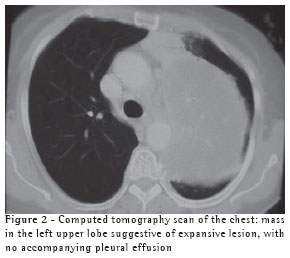

The chest X-ray revealed a dense mass in the upper left lobe (Figure 1).

The computed tomography scan of the chest (Figure 2) confirmed the presence of a heterogeneous mass in the left upper lobe, with air bronchogram adjacent to the mass, suggesting an expansive neoplastic lesion. The patient was unable to produce a sputum sample for testing.

There is no characteristic radiological profile, although the presence of single or multiple nodules that are well defined and not calcified is more common and can mimic neoplasia on the X-ray.(5,9) Radiographic alterations have been reported, including infiltrates (62%), nodules (38%), masses (19%), cavitations (14%) and pleural effusion (3%), without anatomical distribution patterns and without any accompanying hilar or mediastinal lymph node enlargement. Empyema, pneumothorax and pleural involvement suggestive of Pancoast tumor,(13) as well as lung masses invading the chest wall,(14) have also been reported in the literature. A computed tomography scan of the chest corroborates the radiological findings, providing better details for the differential diagnosis,(11) and, when necessary, helps program the invasive diagnostic techniques. In the present case, the patient presented a lung mass that mimicked neoplasia.